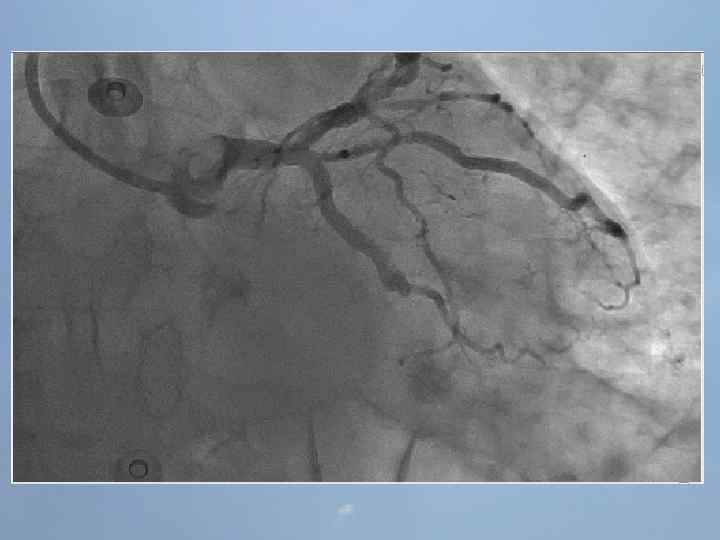

Концепции восстановления кровотока в инфарктзависимой артерии 1. Медикаментозная тромболитическая терапия 2. Рентгенэндоваскулярная – реканализация, БАП и стентирование инфарктзависимой артерии 3. Хирургическая – экстренное аутовенозное или артериальное шунтирование коронарных артерий В настоящее время в мире наиболее эффективным методом восстановления кровотока в инфарктзависимой артерии является коронарная ангиопластика и стентирование Б. Г. Алекян, А. В. Абросимов/Компл. проблемы сер. -сос. заболеваний. 2013, № 1

Преимущества ЧКВ перед ТЛТ 1. Немедленное определение коронарной анатомии и ранняя оценка степени риска 2. Лучшее обеспечение непосредственной проходимости сосудов и адекватного кровотока. 3. Меньшая частота реокклюзий, возврата ишемии, реинфаркта. 4. Лучшая выживаемость пациентов высокого риска. 5. Меньший риск внутричерепных кровоизлияний. 6. Возможность применения метода у пациентов с противопоказаниями к тромболизису. 7. Укорочение сроков госпитализации. • • Недостатки ЧКВ: необходимость в наличии квалифицированных специалиста и ангиографической установки задержка на время подготовки рентгеноперационной Недостатки тромболитической терапии 1. Возможность проведения тромболизиса только у 25 -33% пациентов с ИМ. 2. 20% сосудов после тромболизиса остаются окклюзироваными, а в 45% отмечается сниженный кровоток. 3. Среднее время, необходимое для наступления реперфузии, составляет 45 мин. 4. Отсутствуют клинические признаки, надежно отражающие наступление реперфузии. 5. Возврат ишемии наблюдается в 1530% случаев, внутричерепные кровоизлияния – в 0, 5 -1% случаев. Б. Г. Алекян, А. В. Абросимов/Компл. проблемы сер. -сос. заболеваний. 2013, № 1